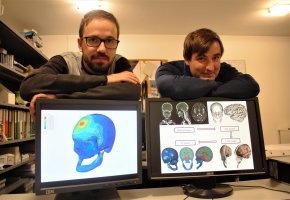

Investigadores do Instituto de Imagem Biomédica e Ciências da Vida (IBILI) da Faculdade de Medicina da Universidade de Coimbra (FMUC) estão à procura de voluntários que queiram participar num estud...